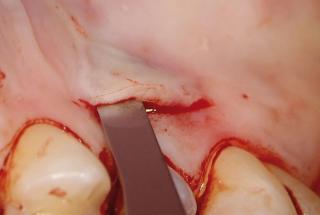

Clinical cases

MPI closely monitors clinical cases in the market to ensure their correct functioning and successful outcome.